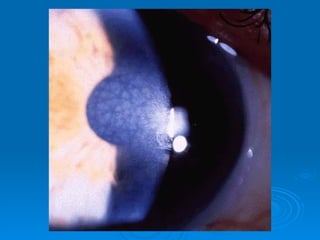

Corneal

Transplantation

If the corneal stroma opacifies due to

trauma or infection, or if there is

swelling or an irregularity of the

surface of the cornea, light cannot

properly reach the retina.

In some cases, a cornea from a

deceased donor can be transplanted.

Corneal Transplantation